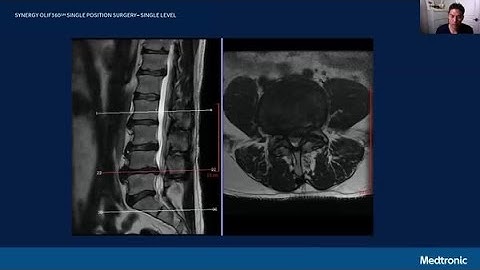

Surgical Case: Mazor™ Robotic Guidance OLIF360™ single-position with an ALIF procedure